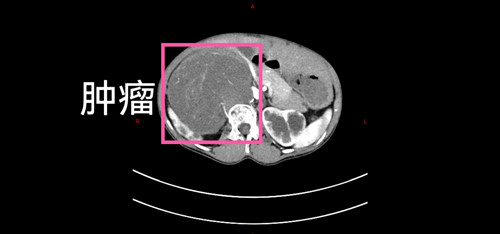

抱着一线希望,家人带着女孩来到了山西省儿童医院普外科。入院后,完善各项检查,结果比预想的更为复杂:初步诊断为节细胞神经母细胞瘤,且已伴有腹膜后广泛转移和盆腔转移。影像学显示,主肿瘤与腹主动脉、下腔静脉紧密粘连,右侧肾动脉甚至穿行于瘤体之中,而盆腔的转移灶与主瘤体不相连。这意味着,手术将如同在血管的“丛林中排雷”,稍有不慎,后果不堪设想。

然而在打开腹腔的那一刻,即使这些经验丰富的医护人员都倒吸一口凉气。由于肿瘤生长时间太长,它已经像一棵根系发达的老树,与周围的正常组织“长”在了一起。特别是与下腔静脉、腹主动脉以及脊柱的粘连,达到了密不可分的程度。每一步分离,都如同在悬崖边行走,需要极致的精细和稳定。

无影灯下,时间仿佛凝固。手术团队凭借着丰富的经验和娴熟的技巧,在血管的缝隙间小心游离,一毫米一毫米地将肿瘤从重要的血管和脏器上“剥离”下来。手术室里的监护仪滴答作响,每一个数字的波动都牵动着在场所有人的心。11个小时,在紧张与专注中悄然流逝。当最后一个瘤体被完整切除,并成功保留了所有重要血管和右肾功能时,整个手术团队才长长地舒了一口气。术中,患儿仅输血2单位,生命体征平稳,安全返回病房。这不仅是一场技术上的胜利,更是一次对生命极限的挑战。